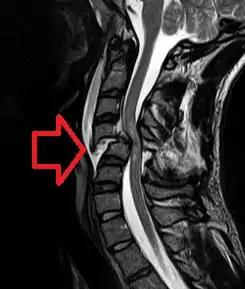

X-rays (left) are more available, but can miss details like herniated disks that MRIs can show (right).[85]

A radiographic evaluation using an X-ray, CT scan, or MRI can determine if there is damage to the spinal column and where it is located.[9] X-rays are commonly available[85] and can detect instability or misalignment of the spinal column, but do not give very detailed images and can miss injuries to the spinal cord or displacement of ligaments or disks that do not have accompanying spinal column damage.[9] Thus when X-ray findings are normal but SCI is still suspected due to pain or SCI symptoms, CT or MRI scans are used.[85] CT gives greater detail than X-rays, but exposes the patient to more radiation,[87] and it still does not give images of the spinal cord or ligaments; MRI shows body structures in the greatest detail.[9] Thus it is the standard for anyone who has neurological deficits found in SCI or is thought to have an unstable spinal column injury.[88]